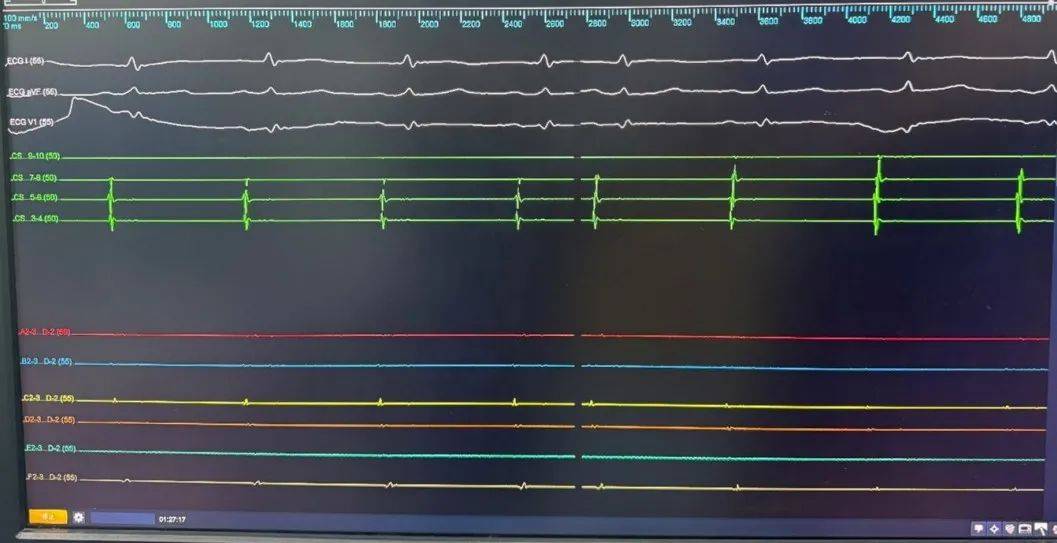

LSPV消融前电位

LSPV消融后电位

LIPV消融前电位

LIPV消融后电位

RSPV消融前电位

RSPV消融后电位

RIPV消融前电位

RIPV消融后电位